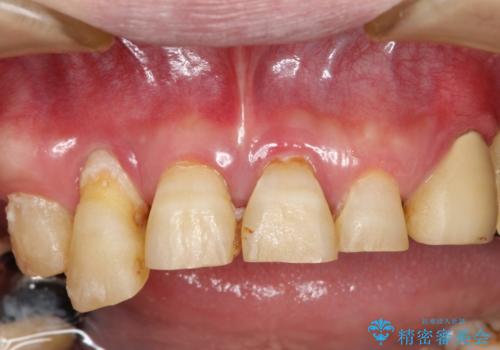

歯周病におかされた前歯の再建治療

- 50代男性

- 1年8ヶ月

- 歯周病により欠損が生じた歯槽骨、まずは再生治療をおこなう